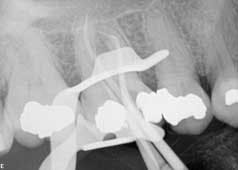

Treatment NSRCT No. 3: 20% topical benzocaine was applied to buccal and lingual injection sites for one minute after being wiped dry with 2x2 gauze. 2x1.8 mL carpules (72mg) 2% lidocaine, 1:100K epinephrine (36 micrograms) buccal (PSA/MSA), and palatal infiltration were administered. Rubber dam isolation was achieved and a bite block positioned to prop the patient’s jaw open. The procedure was performed with the DOM. A bite block was used to help position the patient's jaw in an open position to aid in the initial endodontic access but removed after access was refined. The DOM was positioned at an angle of 60 degrees to facilitate operations while standing over the patient. (Fig. 2) Four canals (MB/MB2, DB, and P) were located with use of anatomical landmarks, DOM, and ultrasonic excavation. Irrigated with 20 mL 6% NaOCl (aids in tissue dissolution, mechanical flushing, lubrication, organic smear layer removal, anti-microbial), 20 ml 17% EDTA (chelating agent, lubricant, removal of inorganic smear layer) RC-Prep (chelating agent, surfactant, lubrication) used with #6-25K-files to resistance. Gates Glidden burs used #2, 3, 4, 1 w/RC Prep. The working length was obtained by close evaluation of preop radiograph and use of an apex locator (RootZX II). The crown down instrumentation (CD) technique was used with Hyflex rotary files (Coltene) and recapitulation was employed throughout the entire procedure. Canals were dried with paper points and Ca(OH)2 (Metapaste) placed within all canals (anti-microbial, tissue dissolution, anti-inflammatory, hygroscopic properties, anti-resorptive and anti-endotoxin agent). Following treatment cotton pellet/Cavit g were placed and postoperative instructions (POI) given verbally and written. The patient was scripted Motrin 600 mg and dispensed 12 tabs, with instructions to take one tab every six hours p.o. for pain (anti-inflammatory, analgesic). The patient was dismissed in stable condition.

Second visit The patient returned to City Endodontics for treatment asymptomatic two weeks later. Rubber dam isolation and access were modified with the DOM; exploration of the distal anatomy was revisited. The distal canal was troughed with a fine diamond tip from an ultrasonic machine (Coltene), and a disto-buccal (DB2) canal located with the aid of the NaOCl 6% bubble test and anatomical landmarks. The DB2 canal was cleaned and shaped to length using same technique used for the other canals at the initial visit. The apex locator Root ZX II was used to confirm presence of an additional canal and reconfirm length for other canals. A check film was taken with files in all five canals to verify presence of five separate orifices and apices. A master cone for all five canals with gutta percha fit to working length was exposed. (Fig. 3)Fig. 3: Master cone fit radiograph of tooth No. 3 highlighting five canals

Figs. 4 and 5: Radiographs of tooth No. 3: Five-canal molar with two mesial and two distal canals present

The obturation technique included warm vertical condensation with continuous wave and AH-plus sealer and backfilled all the canals to their respective orifice. Cotton and cavit g temporary restoration were again placed more than 3 mm from the occlusal surface to prevent coronal micro-leakage in the access cavity. The occlusion checked, postoperative instructions were written and verbally given. Two periapical radiographs were exposed to illustrate the unique anatomy. (Figs. 4 and 5)